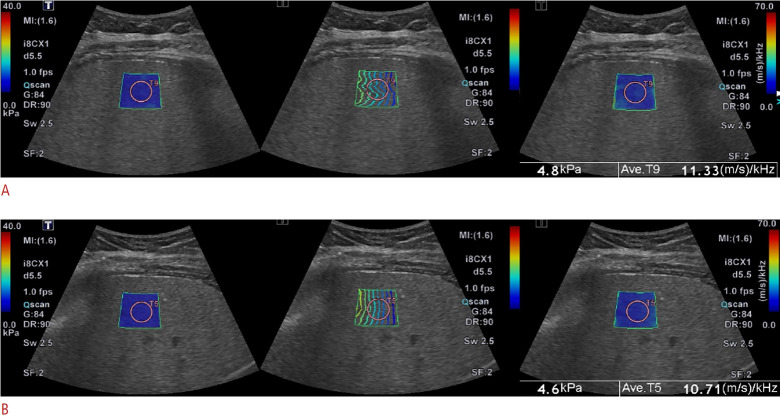

Methods: This study included a retrospective cohort of 163 children and a prospective cohort of 27 children (aged 8-17 years). All participants underwent 2D-SWE and SWD under both free-breathing and breath-hold conditions between September 2021 and February 2023. The prospective cohort also underwent magnetic resonance elastography (MRE). Liver stiffness and dispersion values were compared between respiratory conditions. Inter- and intra-rater agreements were assessed, and correlations with MRE were analyzed in the prospective cohort.

Results: Liver stiffness and dispersion values were significantly higher during free-breathing compared to breath-hold (mean differences: 0.22 kPa and 0.39 m/s/kHz, respectively; both P<0.01). Breath-hold improved inter-rater agreement for 2D-SWE (intraclass correlation coefficient [ICC], 0.94 vs. 0.83; P=0.005) and SWD (ICC, 0.85 vs. 0.70; P=0.048). Intra-rater agreement for 2D-SWE (ICC, 0.88 vs. 0.88; P>0.99) and SWD (ICC, 0.70 vs. 0.74; P=0.396) remained moderate to good and did not differ significantly between conditions. The correlation between 2D-SWE and MRE was stronger under breath-hold than free-breathing (r=0.73 vs. r=0.56), although this difference was not statistically significant (P=0.299).

Conclusion: Breath-holding increases the reliability of pediatric 2D-SWE and SWD by improving inter-rater agreement and correlation with MRE. However, free-breathing also demonstrates comparable reproducibility with minimal bias, supporting its clinical feasibility for use in uncooperative pediatric patients.